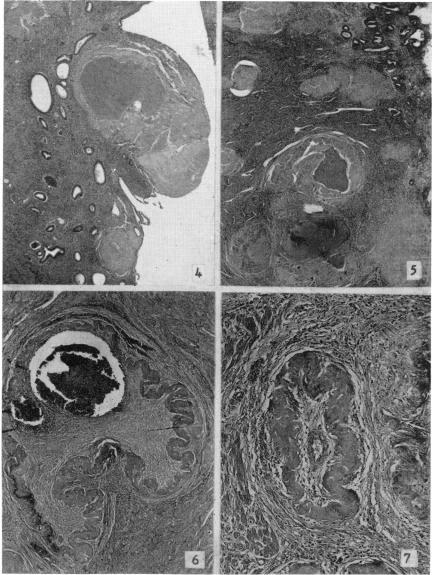

Subinvolution of the placental site.

Bull N Y Acad Med. 1961 Oct;37(10):713-30.

Noninvolution of the placental site.胎盘部位不退化。

Am J Obstet Gynecol. 1959 Oct;78:898-907. doi: 10.1016/s0002-9378(16)36598-x.

Noninvolution of the placental site: clinical and pathological studies.胎盘部位不退化:临床与病理研究

Am J Obstet Gynecol. 1955 Mar;69(3):558-72. doi: 10.1016/s0002-9378(15)30402-6.

Subinvolution of the placental site, a cause of puerperal hemorrhage.胎盘附着部位复旧不全,产后出血的一个原因。